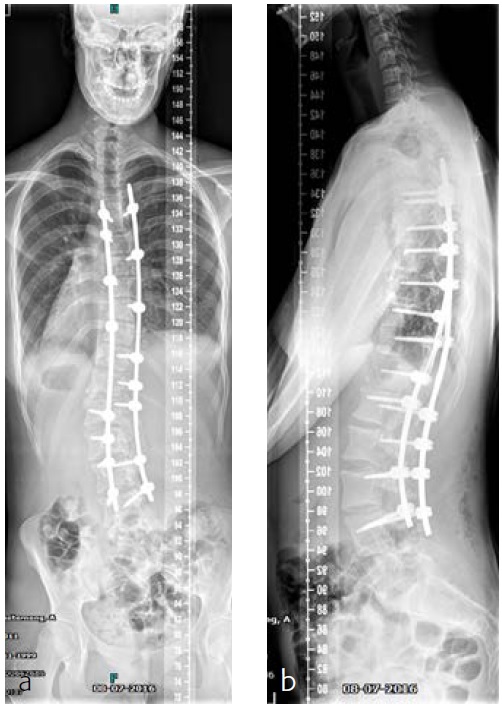

The patient was known and under orthopedic control for a Lenke 5C-type AIS since 2009. Initial treatment with a Boston Brace failed to halt progressive growth, and curve progression became apparent beyond surgical treatment threshold (Fig 9). Bending FS showed TL correction 58 -> 30 (plm 50%). MT correction 43 -> 16 (plm 35%) (Fig 10). The patient was referred to our hospitalfor logistics regarding surgical planning.

After her visit to our clinic, she was planned for surgical correction of the deformity from T5L4 (Fig 11). Surgical procedure with IONM (TC-MEP) postoperative epidural analgesia with the catheter tip at T8. She was mobilised the first postoperative day (Fig 12) and discharged the fourth day after surgery. The patient returned for her 6-month follow-up without any complaints. Limitations are in line with our advice (no sports for 6 months postoperatively). She has no pain and uses no medication.